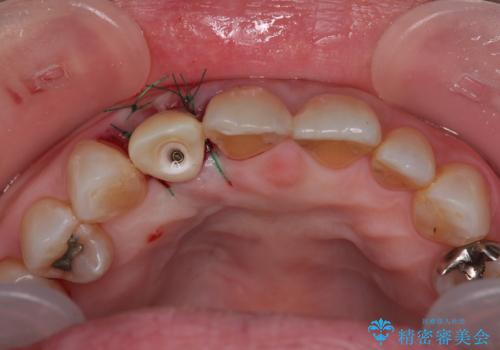

仮歯を事前に用意し、インプラント埋入時に即日で仮歯を装着する、即時荷重インプラントの計画で治療を進めて行くこととしました。

新幹線や飛行機を利用しても来院であり、極力来院回数を減らしたり、東京に用事があるタイミングに合わせてアポイントを調整したりと、負担が少なくなるようにして治療を進めて行きました。

来院間隔があいたため、予定よりも長くなりましたが、大きなトラブルもなく、外科処置は1回のみ、最小の来院数で無事に治療を終えることができました。